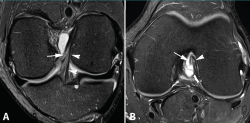

Los hallazgos de RM en las roturas parciales del LCA consisten en un aumento de la señal intrasustancial, defectos focales, distorsión y atenuación de fibras o una orientación anormal del ligamento(1,16)(Figuras 4 y 5). El diagnóstico es más sencillo en fase aguda, por la presencia de signos secundarios con edema y derrame articular. La principal dificultad diagnóstica con RM en la fase aguda consiste en diferenciar roturas parciales de alto grado de completas(1,16).

Figura 4. Rotura parcial del fascículo anteromedial (AM) del ligamento cruzado anterior (LCA) con formación de pequeño ganglión en la escotadura intercondílea. Corte oblicuo coronal (A) y axial (B) de resonancia magnética (RM) potenciados en densidad protónica con supresión grasa que muestran una rotura del fascículo AM (flechas). Fascículo posterolateral normal (cabezas de flecha).

El diagnóstico es más complicado en la fase crónica, especialmente en roturas parciales con resinovialización y cicatrización con fijación al ligamento cruzado posterior (LCP) adyacente. Estas lesiones se pueden confundir con frecuencia con lesiones parciales de bajo grado o con un ligamento normal en la RM. En la exploración clínica estos pacientes muestran generalmente menor laxitud con tope firme(1).

Figura 5. Rotura parcial del fascículo posterolateral (PL) del ligamento cruzado anterior (LCA). Corte oblicuo coronal (A) y axial (B) de resonancia magnética (RM) potenciados en densidad protónica con supresión grasa que muestran una rotura completa proximal del fascículo PL (flechas). Fascículo anteromedial normal (cabezas de flecha).